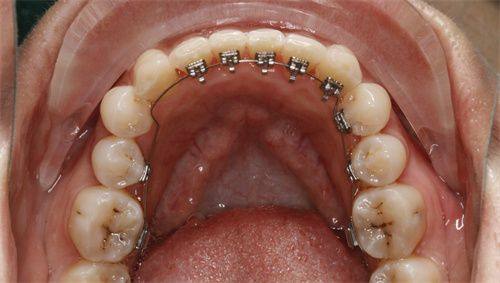

德阳新桥口腔门诊部拥有多个特色项目。种植修复中 心配备了数套代表国内外新型水平的种植系统,以及全新的数字化全景影像系统和独立手术室,为种植修复治疗提供了全力保护。其3D数码隐形正畸技术可以提前预知矫正反应,无论是成人还是儿童,都能在不改变生活习惯的前提下轻松矫正牙齿,让矫正过程更加隐蔽和舒适。此外,门诊部还设有儿童齿科,配备进口儿童专用牙椅,并同步播放儿童喜欢的视频及动画片,以降低儿童就诊的恐惧心理,让儿童在舒适的环境中看牙。

门诊部还引进了众多高端新型的口腔医疗设备,如德国卡瓦种植机、美国3shape口腔扫描仪、意大利NewTom CT等。以种植牙为例,传统种植依赖医生经验,而新桥口腔引入的数字导板技术,能通过CT扫描生成患者口腔三维模型,医生在电脑上提前规划种植位置、角度和深度,手术时像“导航”一样精细,创伤小、修复快,尤其适合牙槽骨条件差的患者。正畸治疗中,iTero口内扫描仪5分钟就能获取牙齿3D数据,患者当场就能看到矫正后的结果模拟,避免了传统取模的异物感和等待时间,儿童患者也能轻松配合。